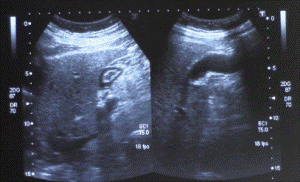

Ecografia Addome

Ecografia Addome Completo, Addome Superiore, Addome Inferiore a Monterotondo

L’ ecografia dell’addome può indagare gli organi dell’addome superiore (fegato, reni, pancreas, milza, e l’aorta) o inferiore (ureteri-pelvi maschile: vescica e prostata, oppure pelvi femminile: vescica-utero-ovaie).